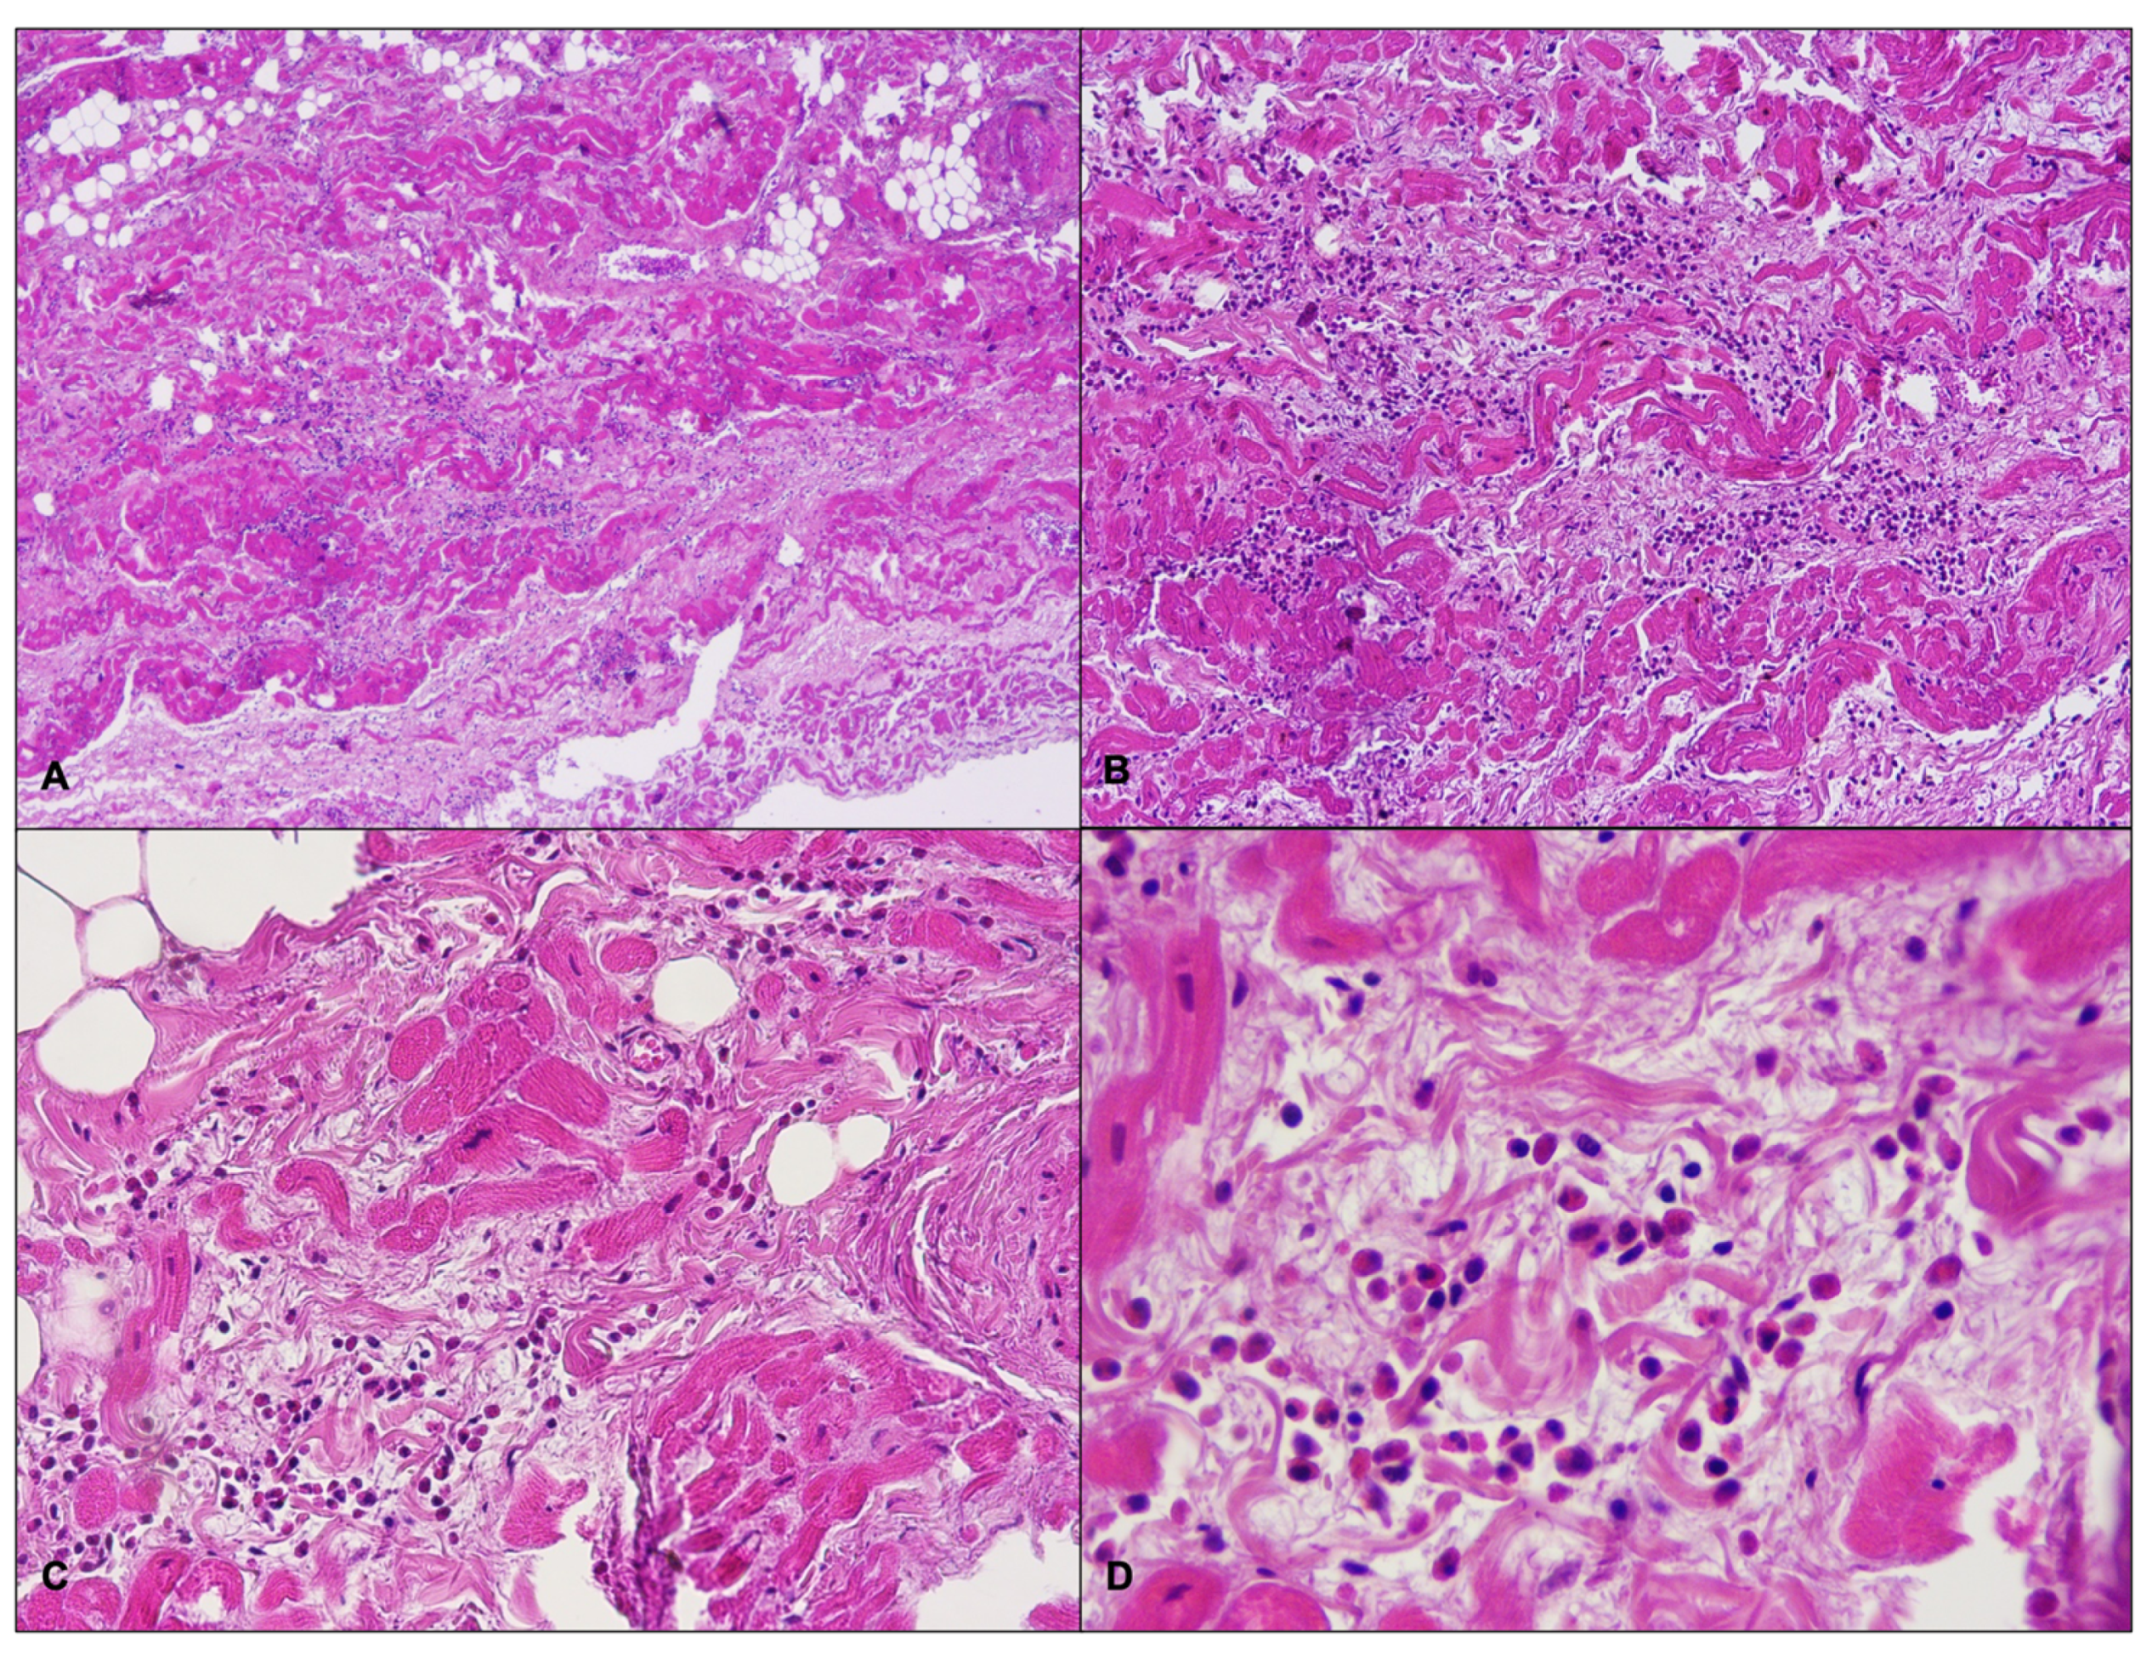

2. Cases Presentation